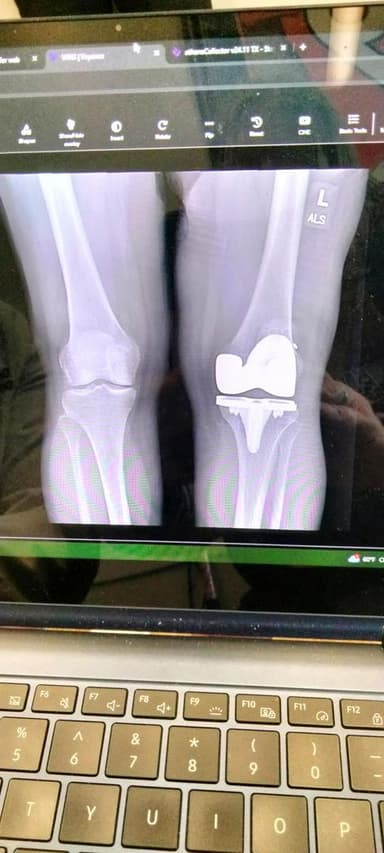

Knee! I've had both of mine done!

I heard the knee surgery is a rough recovery

Right one then I'm having the left one done soon 👍 when I had the right one done I watched on YouTube a knee surgery so I knew what they were going to do to me. I told. my surgeon what I did he said you're braver than him if he didn't do this he would Never watch🤣😂

had mine done too...

I am having tkr with robotic assist on January 13th I am scared to death, like I want to cry listening to everyone say it's aweful

My husband has had a knee replacement, followed by a severe staph infection in that knee, which required months of antibiotics; which did not completely cure the staph; followed by a surgery to clean out the infection; followed by an evaluation that indicated the infection was still active; followed by a removal of the knee replacement and an insertion of an antibiotic spacer for an 8-month period with no knee and a 24-hour antibiotic drip to attempt to eradicate the existing infection; followed by a reinsertion of a new knee replacement and an attempt to remove all the scar tissue from the previous surgeries. Result: a complete chaos. He cannot bend that knee; cannot climb stairs anymore; cannot exercise without pain; cannot walk without a cane or walker; I can go on but you get the picture.

Since we're all sharing our x-rays I figured I'd share mine. I must say that PT was rough! I only did 8 weeks of it at home, and I never did any outpatient PT, so I do still have a lot of pain in the new knee. I've decided against doing the other knee, too painful!

I'm 63 and had both my knees totaled replaced 4 months apart. the first 3 weeks are the hardest after that it was smooth sailing on both of them ice ice ice is your best friend it's been 1 year for the rt knee December 30th and will be 1 year for the left knee on April 21, 2026. Would I do it over again if I had too. YES without a doubt to be able to have my same results I would. 💯‼️

so that piece ends up being his kneecap? The part that goes into his leg bone doesn't look long enough. I've also heard knee surgery is brutal, but every person I know who's had a knee replacement, said the end result was so worth it all! I hope so, because I'm scheduling mine this week. I'm 68 years old. 🙏💕

Knee ,patella .🟦😷🏴☠️

I had a TKR assisted by robotics..on September 25...walked the same day once I came out of re every! stayed over night did PT in hospital...came to my daughter's place followed up by in home PT for the first 2 weeks...used walker 4 maybe 5 times ...did Outpatient PT no biggie! up to 110° range...barely use a cane! happy to say my surgeon gave me clearance to fly to Vegas! in December! an 5 1/2 hour going and coming back! 4 months! doing good...have a uncomfortable feeling at times...like when it rains, its cold & but pretty dam happy over all! right knee next! love my surgeon and his staff ! thanks!!!🙏

I had knee surgery on my right knee and 2023 and I’m still having problems with my knee. It was a Workmen’s Comp. thing so basically I got screwed.!!!!

knee replacement thats the kneecap

wowser ...now I know what my knee looks like...it was a good year from the surgery till basic recovery--- still bother me if I try to actually kneel down on it for long..its getting better still

I had total replacement on both knees, not that bad. Better than the pain before surgery. Nerves take awhile to regenerate.

I've had both my knees totally replaced. One in 1999 and the other in 2001. They say a replacement knee only last 12 to 15 years before you would need to have it replaced again. So far I've lucked out. I had a fantastic surgeon. It is now 2026 and I still have both knees and haven't needed the 2nd replacements. I don't have pain in either one of them. Just a little stiffness getting up if I sit too long. I obtained my surgeon through Cleveland clinic sports medicine. The doctor I had is now retired. His name was Doc Brooks. I thank him everyday for a job well done. If I didn't have the surgery, I would have been in a wheelchair right now.

Knee cap

Looks like the prosthetic component for the medial condyle of the femur and it’s quite possible that it’s part of a Total Knee Arthroplasty.

This is a partial knee joint replacement. I help put them in everyday except Friday Saturday and Sunday..Upper part.

This xray is revision surgery repair of snapped patellar tendon after total knee replacement. Recovery after this surgery required 8 weeks in a full leg cast (non weight bearing) miserable surgery, recovery and physical therapy!

I had a partial and 8 months later , STILL having a significant amount of pain....

I have 3 screws and surgical wire holding my knee cap closed. My first break of a bone, ever!! I was 70.. I did all PT and have good range of motion, an injection or 2.. Tylenol is all I need now! Y’all be careful, it seems home can be dangerous!

I JUST HAD KNEE SURGERY ON MY LEFT KNEE ON OCTOBER 20TH 2025 ,MY RIGHT KNEE IN JANUARY OF 2020,THEY MESSED UP MY KNEE,BUT THEN A CAR HIT ME 4 MONTHS AFTER MY KNEE SURGERY,IT MESSED IT UP MORE, WAITING TO SEE IF THEIR GOING TO RE-DO MY RIGHT KNEE AGAIN🙏💕

Knee

I had a tkr and have issues. Surgery was wonderful (Great Surgeon). My knee range of motion was 60%. Had to an anesthesia manipulation therapy which setback my recovery due to an avulsion fracture from the AMT. After 4 months, I'm finally beginning to feel better and walk with a cane. You will need to take the pain meds at first to be able to sleep. Everybody heals differently. Do your research and make sure you're ready for the process. ❤️ 🙏

Had my right knee done, it was painful but overall happy I had it done.

Something with a knee. Kneecap? Ive got a lot of hardware in mine...three surgeries on the same knee. The third one finally worked right. Scar got bigger with each one.

Looks like implant for knee replacement. You don't realize the stress you put on your knees, until they start mocking you with every step.

I had my right knee done, it was easy on me. 2 months later I had my Left knee done and it was way harder. But my right was way easier.